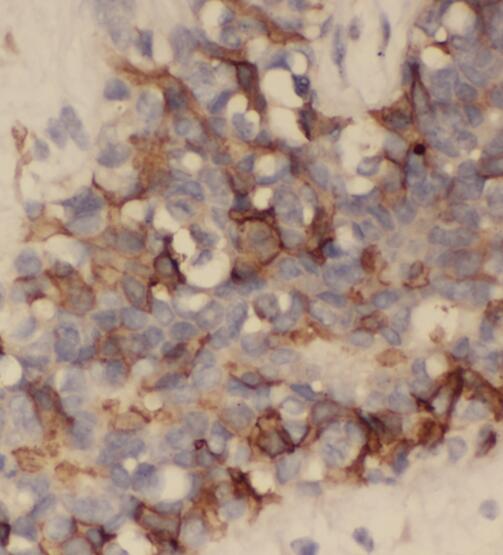

Immunohistochemistry of paraffin-embedded human breast cancer using FNab06531(PLDN antibody) at dilution of 1:50 IP Result of anti-PLDN (IP:FNab06531, 3ug; Detection:FNab06531 1:500) with K-562 cells lysate 3600ug.